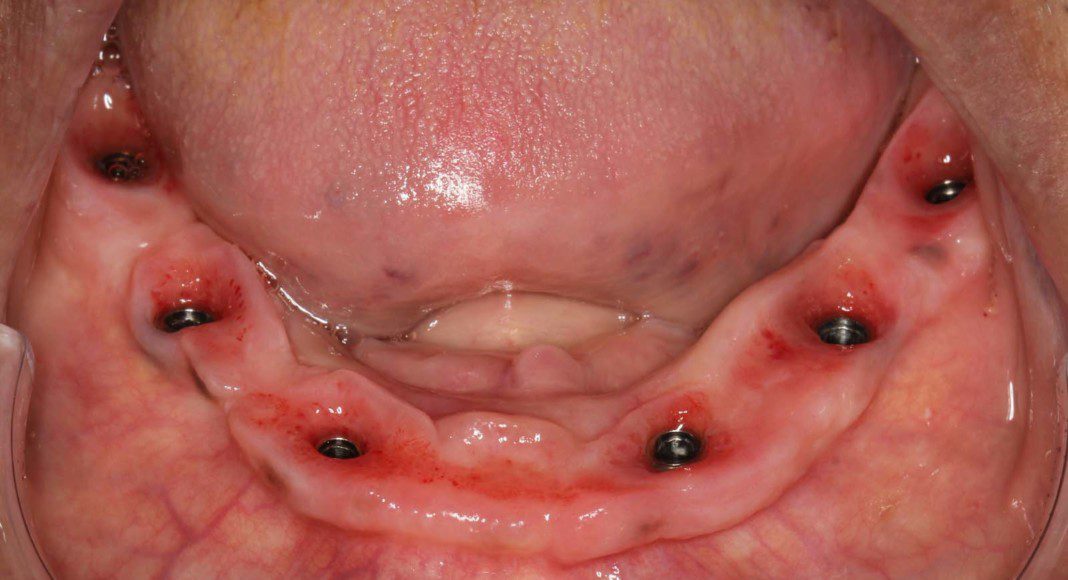

Lower titanium/ acrylic (titanium skeleton/ acrylic wrapped and retained to the titanium) bridge in mouth. Occlusal view.